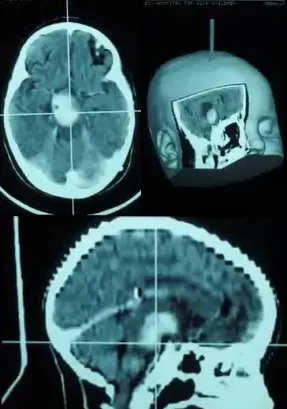

"从核磁共振的影像来看,孩子脑子里确实有一个肿瘤,长在中脑被盖——这是大脑深处最核心的区域,四周密布着控制眼球运动和肢体协调的神经核团。手术在技术上是可以做的,但风险也是客观存在的……"

手术排在工作日上午进行。Rutka教授采用了经胼胝体入路,通俗地讲,就是绕开大脑最繁忙的区域,借助大脑半球之间一条天然形成的间隙进入,直抵肿瘤所在位置。这就好比不拆墙,而是从门缝里将手伸进去把东西取出来。

与此同时,手术全程配合了图像引导技术,相当于给操作器械安装了GPS定位系统。屏幕上实时呈现器械所在坐标,误差范围几乎可以忽略。手术历时数小时。当Rutka教授走出手术室,开口告诉小乐妈妈"肿瘤全切了,孩子状态很好"时,小乐的妈妈双腿一软,险些跪倒在地。

复视(看东西出现重影)、行走不稳、头痛、恶心呕吐,这几组症状组合在一起,恰好构成了中脑被盖胶质瘤的典型临床表现。局灶性被盖部位的肿瘤,无论是手术入路的选择还是术后的长期管理,对神经外科医生来说都是一项巨大考验。这类病变大多数属于低级别胶质瘤,可以通过有框架或无框架立体定向活检的方式获取病理诊断。可供选择的手术入路包括经外侧裂入路、经颞叶入路以及经胼胝体入路,具体采用哪种方案,需结合肿瘤的体积以及其与软脑膜或脑室表面的位置关系综合判断。